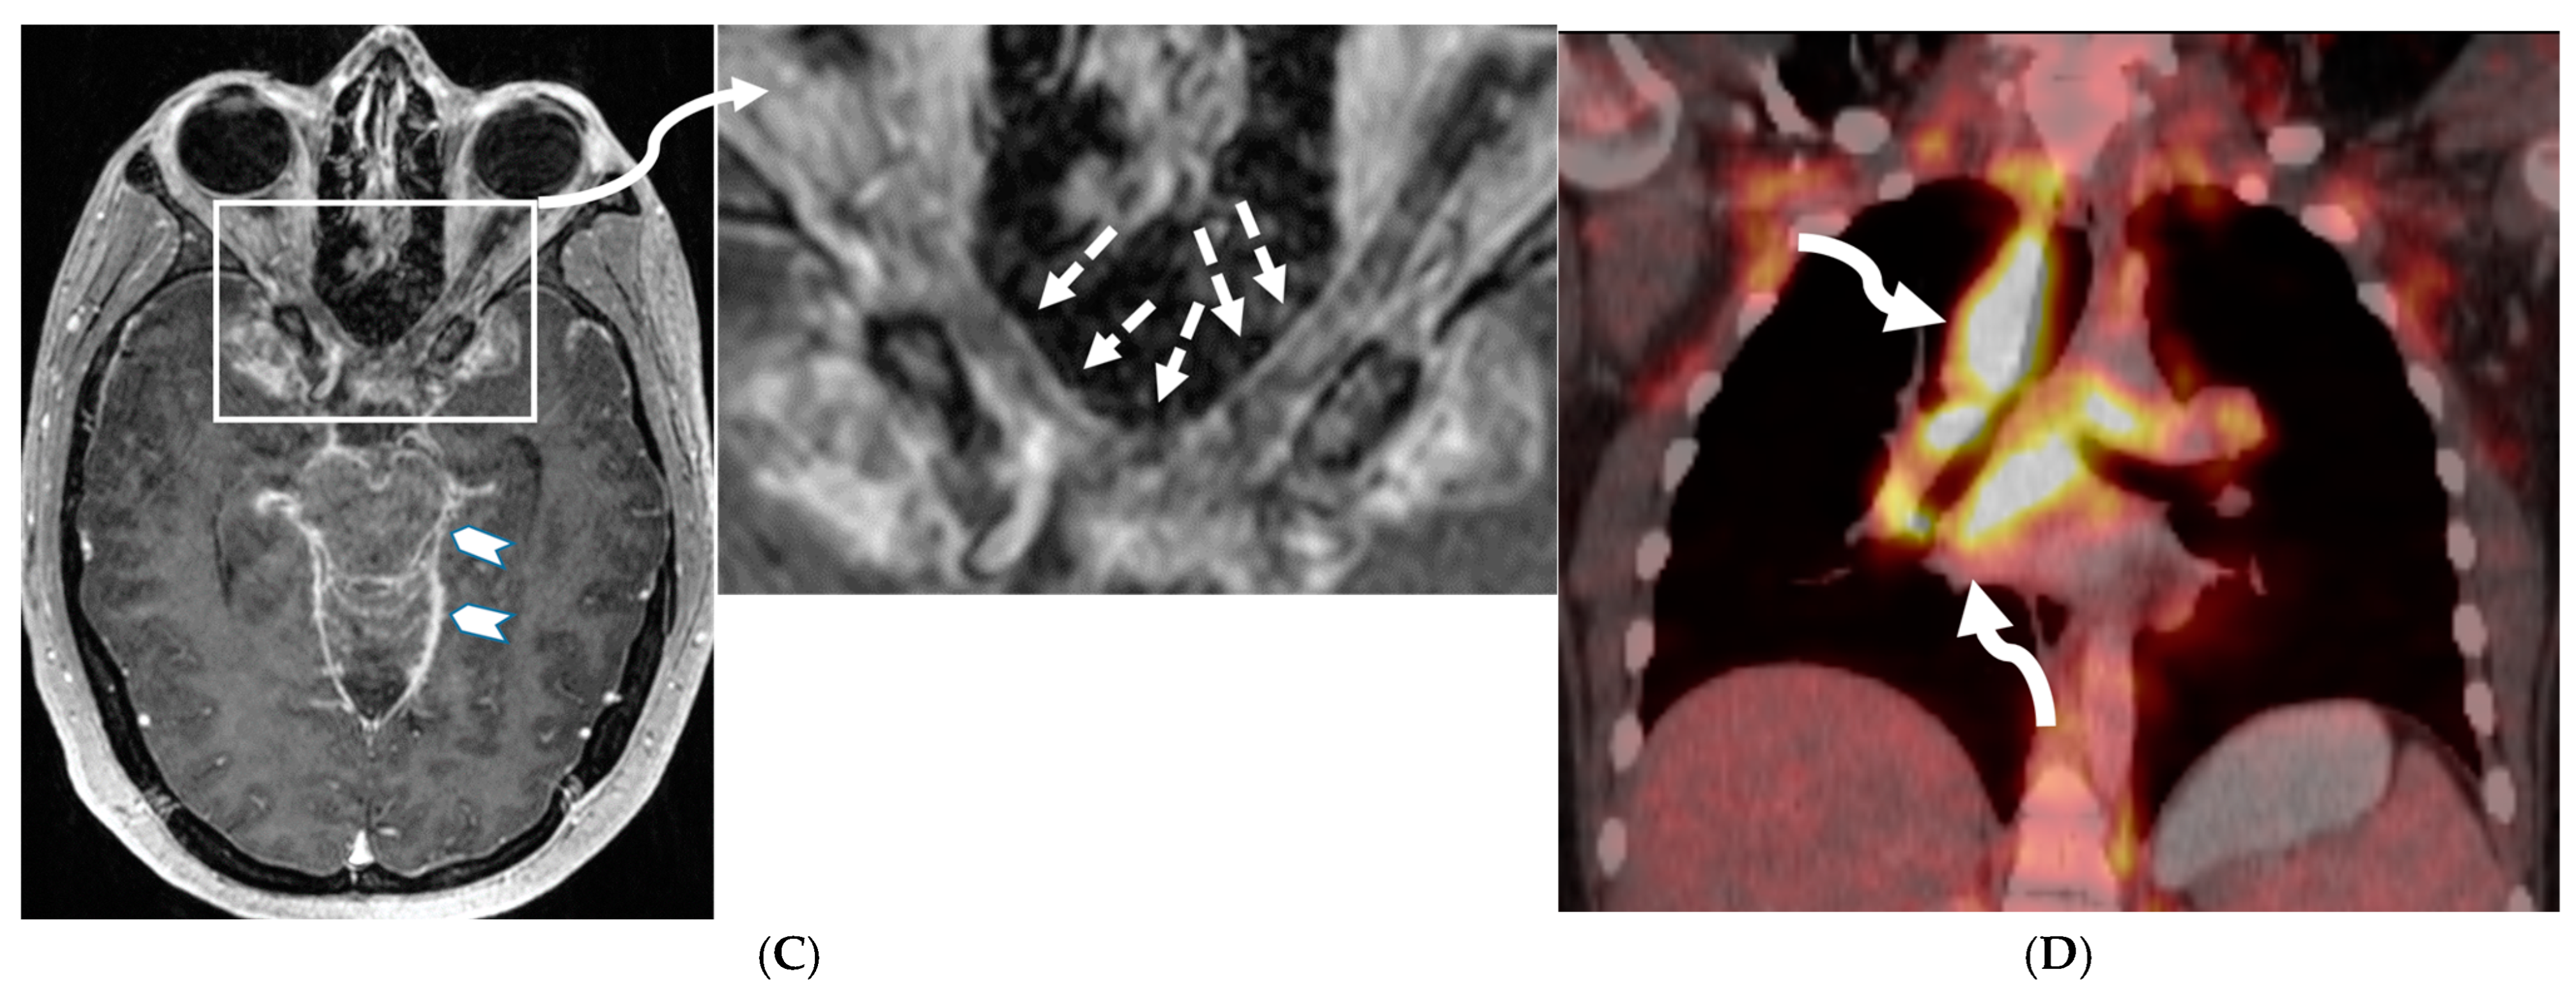

Figure 5.

Axial CT (A,B), axial T2 fat saturated (FS) (C), Axial Diffusion Weighted Imaging (DWI) & Apparent Diffusion Coefficient (ADC) (D,E), axial and coronal post contrast (F,G): 15-year-old girl with nausea and headaches. CT shows iso-dense dural-based mass in the left anterior cranial fossa (arrow). Adjacent bone is hyperostotic and has irregular cortex (curved arrow). The lesion is isointense with cortex, which is buckled inwards from the mass. A hyperintense rim surrounds the mass representing CSF cleft (dashed arrow). No significant restricted diffusion is noted. The mass enhances intensely and uniformly. A dural tail (open arrow) of benign, nonneoplastic reactive thickening is present adjacent to the left frontal mass, characteristic of classic “typical” WHO grade 1 meningioma.